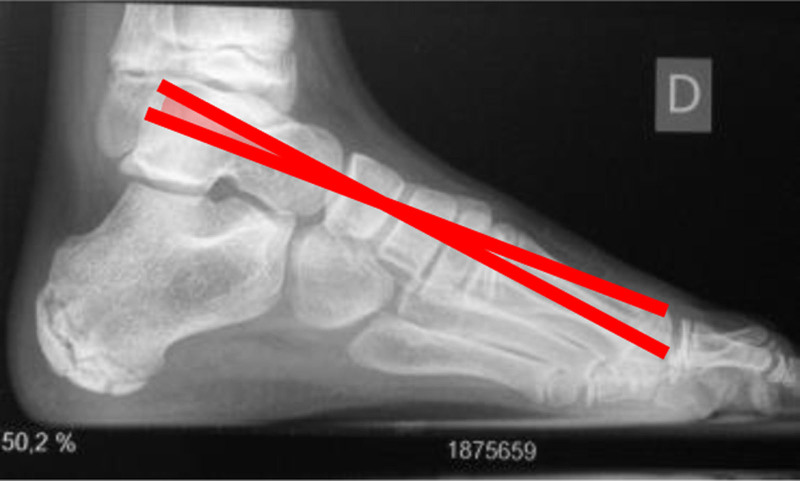

The objective of this study is to describe and evaluate dorsal hemiepiphysodesis of the first metatarsal as an osteotomy replacement technique. Retrospective analysis of patients with pes cavovarus (PCV) treated in our center with dorsal hemiepiphysodesis of the first metatarsal. Meary's angle, calcaneal pitch, and Moreau Costa Bartani were compared pre and post-operatively and the ratio between width and foot length was monitored. Between May 2012 and May 2022, eight patients (14 feet) with PCV underwent dorsal hemiepiphysiodesis of the first metatarsal combined with the Steindler procedure. Four patients (50%) were male. The average age for boys at surgery was 10.75 years (10-11) and for girls was 9.75 years (8-11). Most patients (87.5%) had idiopathic PCV and 12.5% had a neurological PCV. Median follow-up was 4.3 years (1.5-10) and a benefit was seen in all patients in Moreau Costa Bartani angle (112.64° vs. 120.59°; P value = 0.003), calcaneal pitch (26.48° vs. 25.36°; P value = 0.091) and Meary's angle (10.60° vs. 5.36°; P value = 0.008) after surgery. Supination improvement was also shown (0.21 vs. 0.24; P value = 0.039). Despite the limited number of patients, the results demonstrated that dorsal hemiepiphysiodesis of the first metatarsal can be a valid alternative to osteotomy of the base of the first metatarsal, with less morbidity and a gradual and dynamic correction throughout growth.

Abstract Image